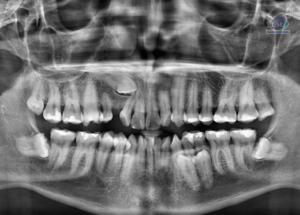

Paciente masculino de 09 años de edad acude al Instituto de Diagnóstico Maxilofacial para una tomografía de campo mediano (10 x 10mm) con el motivo

Paciente masculino de 22 años acude al Instituto de Dianóstico Maxilofacial para realizarse una tomografía macizofacial para la colocación de ortodoncia. A la evaluación de